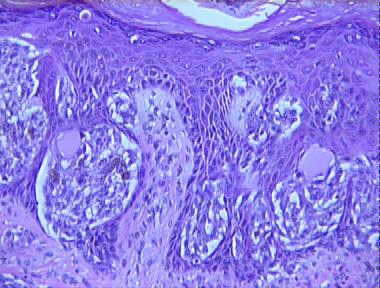

compound Spitz nevus

Histologic Features

- Hyperkeratosis, hypergranulosis and irregular epidermal hyperplasia

- Nest of large spindle melanocytes mostly at the dermo-epidermal junction

- Nests predominating over single cells

- Clefts between nests and epidermis

- "Kamino" bodies associated with the nests

- Scatter of single melanocytes above the dermo-epidermal junction

- Irregular nests of spindle and epitheliod melanocytes in the dermis

- Maturation of nevus cells with descent

- Fibroplasia and telangiectasia of the upper dermis

- Lymphocytic and plasmacytic infiltrate around the blood vessels

- As a whole, the lesion is not very large (less than 1 cm.), symmetrical and well-circumscribed.